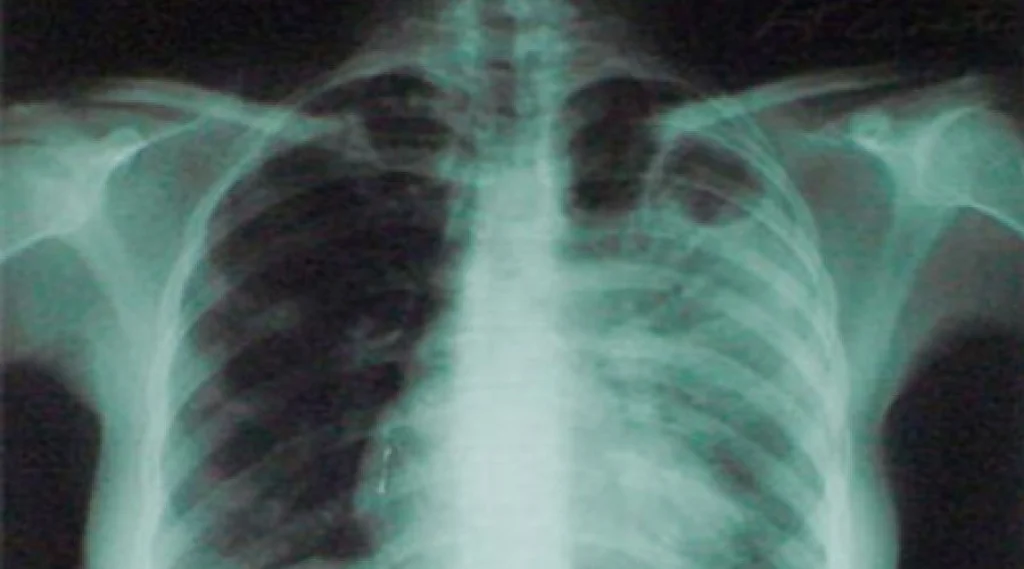

42-летний житель Киреевска состоит на учете в медчреждении с диагнозом – инфильтративный туберкулез легких. Заболевание развивается в активной форме, он запросто может заразить окружающих в ходе бытового общения. Однако, больной уклоняется от лечения и нарушает санитарно-эпидемиологический режим.